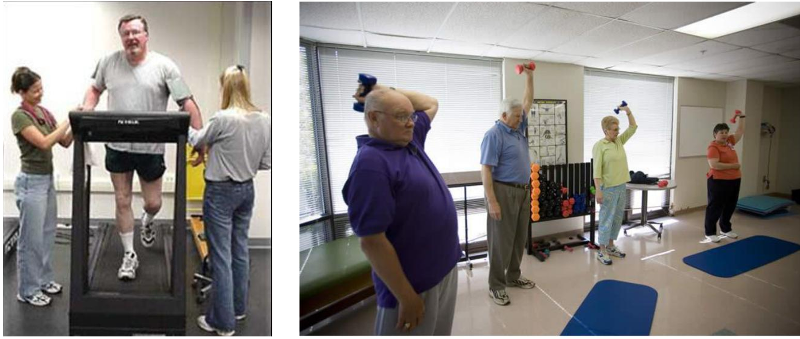

Read MoreCARDIAC REHABILITATION

Regain full physical, psychological and social status Optimize long-term prognosis To promote and implement secondary prevention measures Exercise training, education sessions, psychosocial support and support/counselling for patient and family in acute phase, out-patient care and long-term follow-up. Decrease cardiac morbidity and relieve symptoms Risk modification and secondary prevention Decrease anxiety and increase knowledge and self-confidence […]